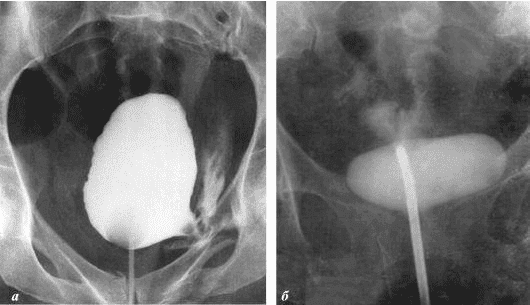

Ich möchte Ihnen ein paar Fotos zeigen, um zu zeigen, was im Urogenitalsystem und anderen Organen eines Mannes vor sich geht, der keinen Sex hat.

So sieht eine Entzündung der Prostata aus, die durch Stagnation der Spermien verursacht wird (wenn die Hoden nicht geleert werden). Eine anhaltende Entzündung führt zuerst zu einem Prostataadenom und dann zu Krebs. Dies ist eine unvermeidliche Folge von Prostatitis, daher wird es als "Krankheit der älteren Generation" bezeichnet.

Prostatakrebs bei einem Mann mit 58 Jahren.